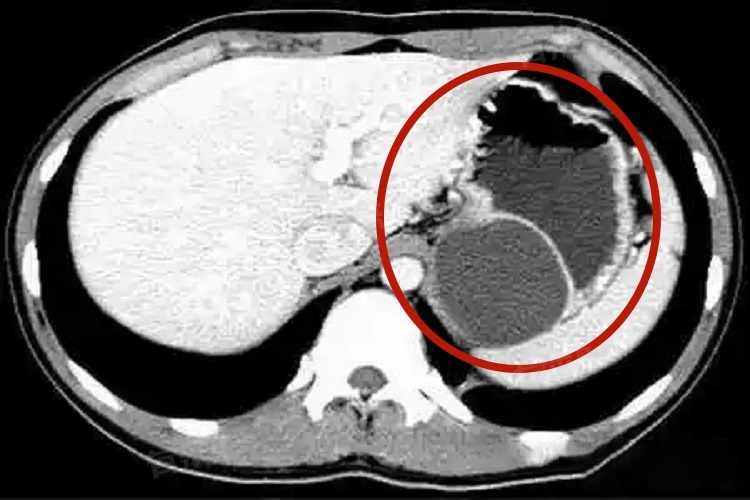

胃囊肿是指胃壁出现囊性肿物,其内部含有液体或半固体物质。囊肿可以发生在胃的任何部位,从胃黏膜层到浆膜层都有可能。它是一种相对少见的胃部疾病,通常是良性病变,一般情况下不严重。

若出现上腹部隐痛、胀满、恶心呕吐、食欲减退,甚至呕血黑便等症状,需警惕胃囊肿,应及时就医。挂消化内科,通过胃镜、超声胃镜、CT等检查明确诊断。无症状小囊肿多定期复查;有症状或较大囊肿,依病情遵医嘱选内镜或手术治疗。